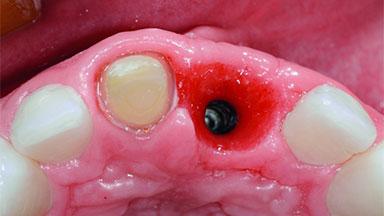

Replacement of an Ankylosed Upper Left Central Incisor: Bone Augmentation and Socket Grafting, Late Placement of an RC Bone Level Implant

| # of Teeth | 1 |

| # of Implants | 1 |

| Type of Implants | Two-Piece |

| Placement Protocol | Early or late implant placement |